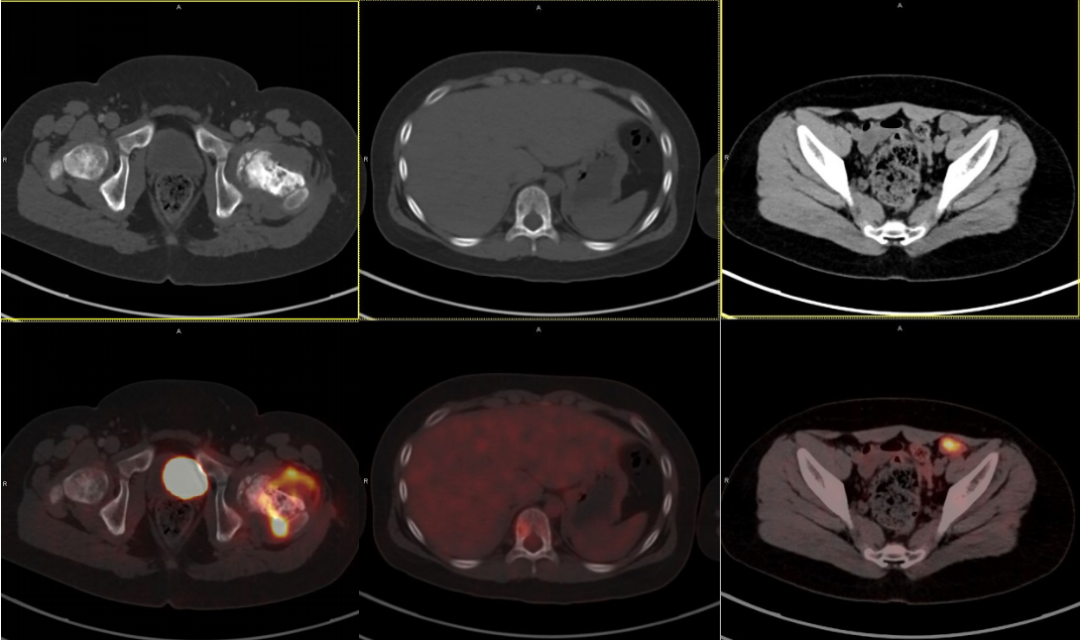

小宇的 PET/CT 检查结果,瞬间揭开了病情的全貌,远超之前的想象:

原发灶确认:左股骨原发病灶区域呈现显著的放射性浓聚(高代谢),符合尤文肉瘤表现。

髓内跳跃转移:在左股骨本身、距离原发灶有一段距离的中段髓腔里,也出现了异常的放射性浓聚灶!这意味着肿瘤细胞已经沿着骨髓腔悄悄蔓延,形成了「髓内跳跃转移」。这种早期、微小的骨髓内扩散,在常规 CT 甚至 MRI 上都非常容易被遗漏!

远处骨转移:扫描范围扩大到全身,一个刺眼的「亮点」出现在胸 10 椎体。脊柱骨转移被明确发现。

淋巴结转移:在左侧髂外血管旁可见一枚肿大淋巴结并异常放射性浓聚,提示存在区域淋巴结转移。

一次检查,全景浮现! PET/CT 的结果清晰勾勒出小宇体内尤文肉瘤的「势力范围」:局部晚期(存在髓内跳跃转移和区域淋巴结转移)伴远处骨转移。疾病被精准地分期为 IV 期(晚期)。这个结果虽然沉重,但却是制定有效治疗方案不可或缺的基石。